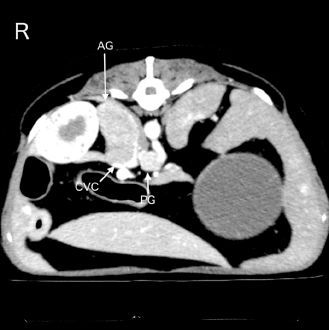

The dog was scheduled to undergo contrast-enhanced computed tomography (CT) with 300 mg iodine/ml iohexol (Omnipaque 300 injection; Daiichi Sankyo Co., Ltd., Tokyo, Japan) at 2 ml/kg for surgical planning of adrenalectomy 7 days after the initial examination at our hospital. A 22-gauge, 31-mm intravenous (IV) catheter (Supercath5; Medikit Co., Ltd., Tokyo, Japan) was placed in the cephalic vein, and general anesthesia was induced with IV administration of butorphanol (Vetorphal; Meiji Animal Health Co., Ltd., Tokyo, Japan) and propofol (PropoFlo; Zoetis Japan, Tokyo, Japan). After intubation, anesthesia was maintained using oxygen and isoflurane (Isoflu; Zoetis Japan, Tokyo, Japan). The electrocardiogram, pulse rate, RR, end-tidal carbon dioxide concentration, indirect mean arterial pressure (MAP), and percutaneous oxygen saturation (SpO2) were monitored using a multiparameter monitor (BSM-5192; Nihon Kohden Corporation, Tokyo, Japan). During the CT scan (Aquilion PRIME; Canon Medical Systems Corporation, Tochigi, Japan), intermittent positive pressure ventilation was maintained. The patient’s pulse rate ranged from 58 to 79 beats/minute, and MAP ranged from 68 to 79 mmHg during anesthesia. The time from the induction of anesthesia to extubation was 24 minutes, and recovery from anesthesia seemed to be very smooth. The dog was moved to the ward after spontaneous head lift was observed. CT scans showed a right adrenal gland mass invading the caudal vena cava (Fig. 1). In addition, the mass around the celiac and cranial mesenteric arteries was consistent with a previous report of paraganglioma (Gombert et al., 2022) (Fig. 1). The CT images of the lungs appeared normal, except for some bullae (Fig. 2A and B).

Fig. 1. An abdominal CT image of the present case is shown. A right adrenal gland mass with invasion of the caudal vena cava is observed. In addition, a mass around the celiac and cranial mesenteric arteries, suggestive of a paraganglioma, is also detected. AG, adrenal gland mass; CVC, caudal vena cava; and PG, the mass suspecting a paraganglioma.